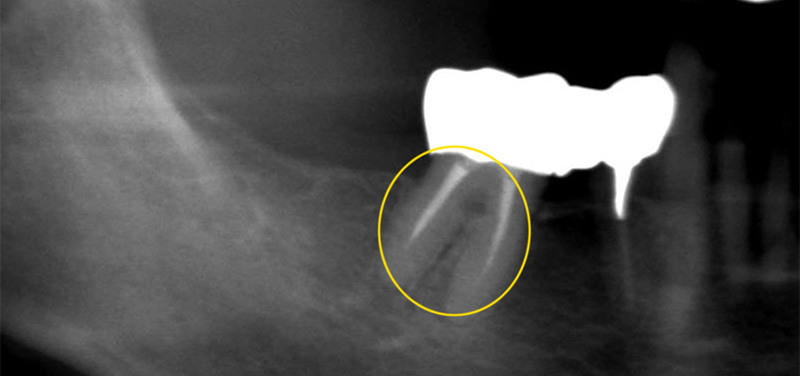

かぶせ物ではなく、ダイレクトボンディングでの治療、また埋入されているインプラント体に問題はなかったため、仮歯のやりかえと上部構造物の製作を行いました。